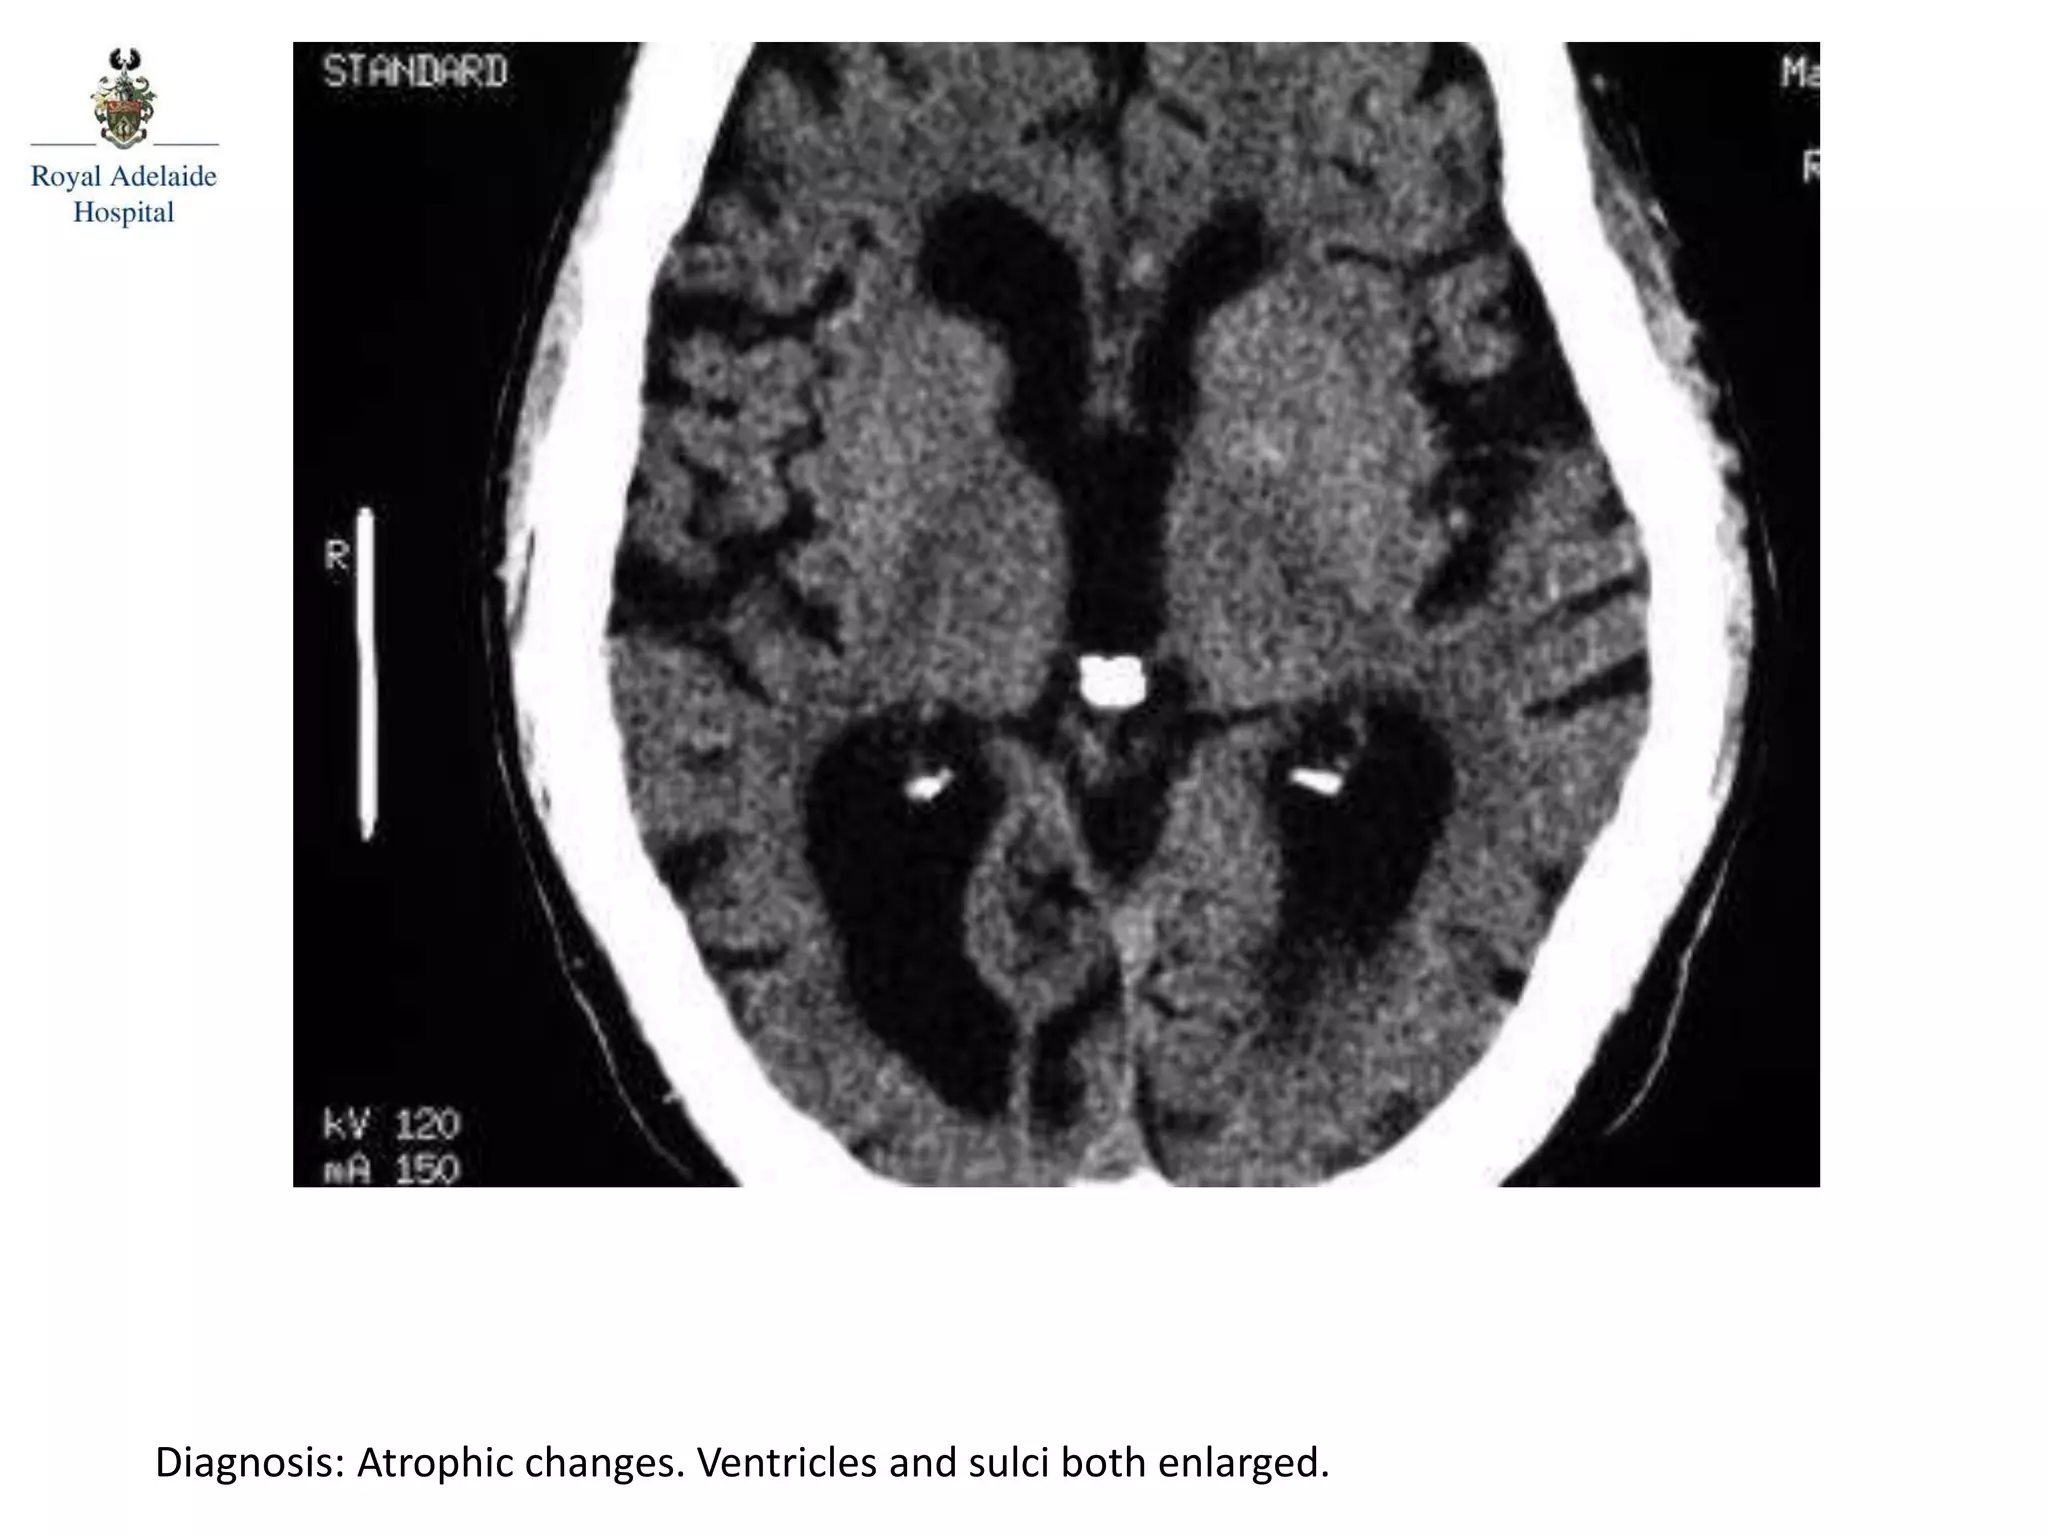

The document outlines multiple diagnoses from head CT cases, including small left basal ganglia bleed likely due to hypertension, various types of subdural and subarachnoid hemorrhages, and evidence of hydrocephalus. It details traumatic origins of some hemorrhages and notes obstructing masses and atrophic changes. Overall, there are significant findings indicating complications related to cerebral hemorrhages and ventricular enlargement.